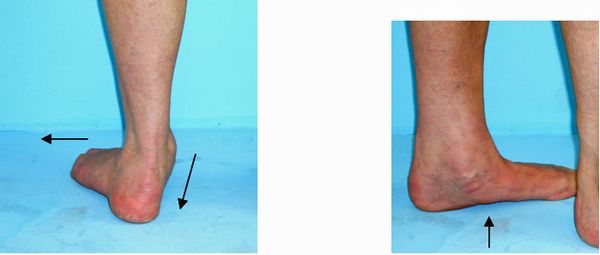

Klinisch bestehen Druckschmerzen und Schwellungen im Verlauf der Sehne hinter und unterhalb des Innenknöchels. Die Absenkung des Fußlängsgewölbes ist mit bloßem Auge zu sehen. Hinzu kommen eine valgische Fersenfehlstellung und eine vermehrte Vorfußabduktion (Abweichung des Vorfußes nach außen).

Abb.2: Der Vorfuß weicht nach außen ab. Das Fersenbein knickt ein. Das Fußlängsgewölbe ist aufgehoben.